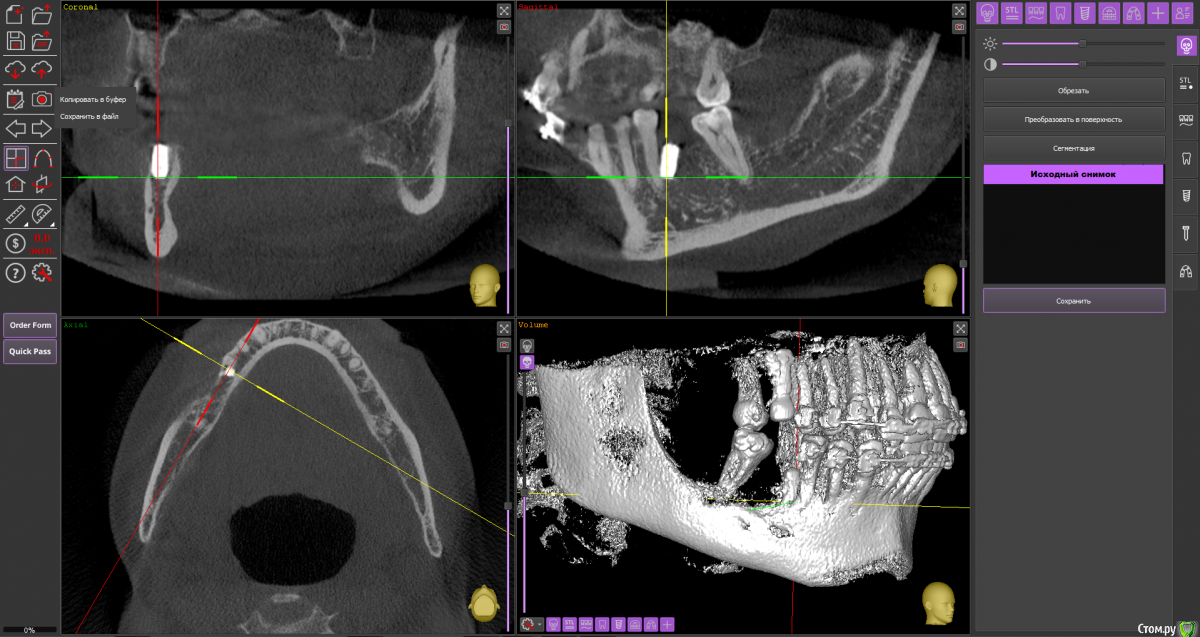

Тата Богачевская Опубликовано 24 октября, 2020 Поделиться Опубликовано 24 октября, 2020 Здравствуйте. Меньше месяца назад на место отсутствующего 46 зуба мне был установлен имплантат с расщеплением альвеолярного гребня. Операция прошла хорошо, никаких осложнений. В настоящий момент ничего не беспокоит. Тем не менее положение имплантата у меня вызывает беспокойство - слишком близко к корню 45 зуба и под углом к нему. Однако доктор уверяет, что положение имплантата нормальное, не идеальное конечно, но не критичное. Скажите, пожалуйста, угрожает ли такое положение имплантата 45 зубу, возможно ли будет в дальнейшем установить коронку в правильное положение? Или нужно удалить имплантат? Благодарю.https://yadi.sk/d/Tzd1aKb84eU3wQ Ссылка на комментарий

Тата Богачевская Опубликовано 25 октября, 2020 Автор Поделиться Опубликовано 25 октября, 2020 1.png2.png3.pngВы сделали то, что попросил red butler? Это и есть срезы? Большое спасибо. Ссылка на комментарий

red_butler Опубликовано 25 октября, 2020 Поделиться Опубликовано 25 октября, 2020 Имплант нужно переставить Ссылка на комментарий

колесников Опубликовано 25 октября, 2020 Поделиться Опубликовано 25 октября, 2020 4 месяцаИмплант 46 нужно убрать. Зуб 47ой дистализировать ортодонтически. Переустановить имплант 46 в правильной ортопедической позиции с десневой пластикой. К окончанию лечения вероятно будут вопросы к импланту 16,положение его платформы не самое оптимальное . 1 Ссылка на комментарий

колесников Опубликовано 25 октября, 2020 Поделиться Опубликовано 25 октября, 2020 (изменено) Поясните пожалуйста понятным для пациента языком, что значит "положение платформы 16 имплантата не самое оптимальное" .Я только на панорамный снимок ориентируюсь,возможно все не так как кажется. Мне представляется так:чтобы поставить клык (13) в зубной ряд,надо дистализировать 15,14 ,что создаст проблем для протезирования 16,который уже сейчас близко к 15 ,для моделирования коронки моляра 16. Вначале ортодонтия,после имплантация. Немного поторопились с имплантами. Или придётся удалить 15,чтобы не трогать имплант 16 Изменено 25 октября, 2020 пользователем колесников Ссылка на комментарий